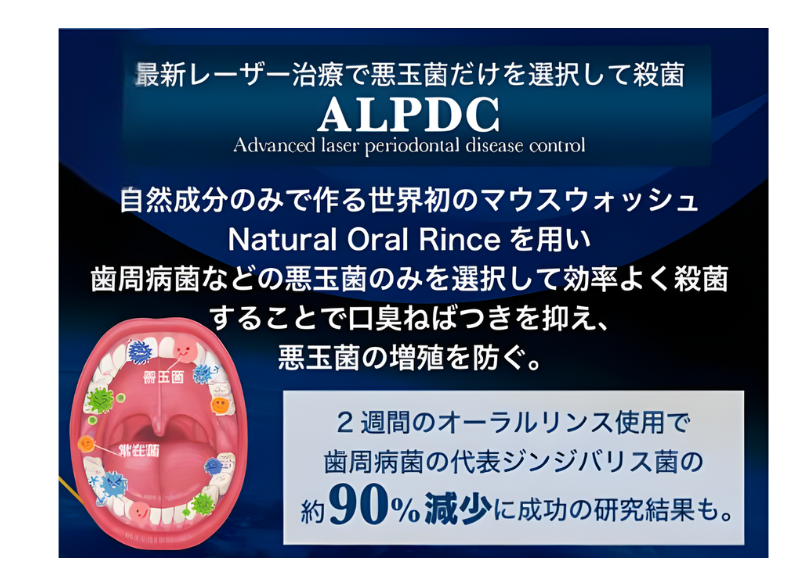

口腔内環境を育てる「ALPDC療法」という新発想

そこで当院ではクリニックでの専門的な治療に加え、ご自宅でのセルフケアの質を飛躍的に高めるための新しい考え方を取り入れています。

それが「ALPDC療法」です。

殺菌から「整菌」へ

従来のオーラルケアはお口の中の菌をすべて「殺菌」することに主眼が置かれていました。

しかし強力な殺菌剤は悪玉菌だけでなく、お口の健康を守るために必要な善玉菌まで殺してしまい、かえってお口の中の細菌バランスを乱してしまうことがあります。

ALPDC療法の考え方は「整菌」です。

腸内フローラと同じようにお口の中にも細菌叢(さいきんそう)、すなわち「口腔内フローラ」が存在します。

悪玉菌の活動を抑制し、善玉菌が優位な環境を育てることでお口の中フローラのバランスを整え、歯周病菌が増殖しにくい健康な口内環境そのものを創り上げていく。これがALPDC療法の目指すところです。

ALPDC™マウスウォッシュ・ジェルの役割

この「整菌」という考え方をご自宅で実践していただくために開発されたのが「ALPDC™マウスウォッシュ・ジェル」です。

この製品には人由来の乳酸菌(善玉菌)が作り出す抗菌物質が配合されており、悪玉菌の活動を選択的に抑制する働きがあります。

化学物質やアルコールを一切使用していないため、お口に優しく毎日安心してお使いいただけます。